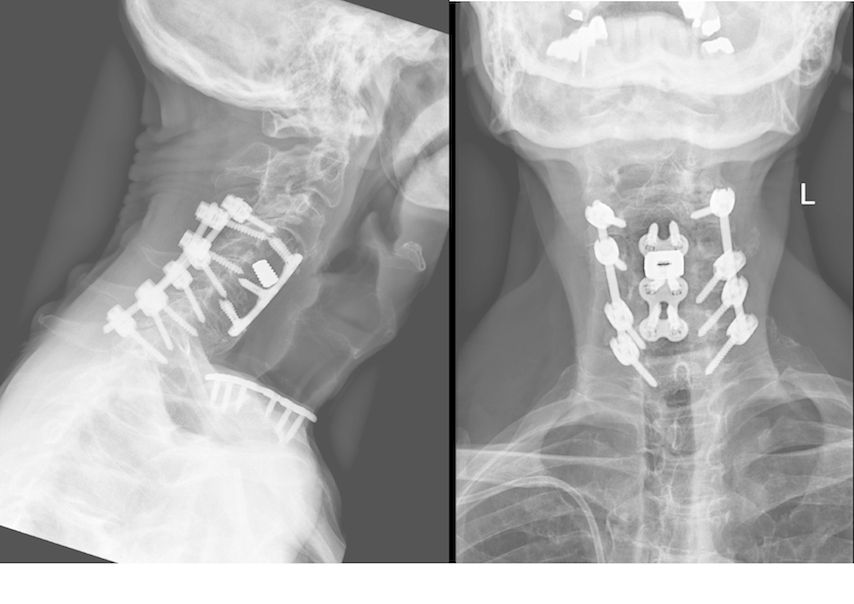

Beispiel für die Implantation zervikaler Pedikelschrauben. In diesem Fall kam es bei einem 61-jährigen Patienten 10 Jahre nach anteriorer zervikaler Diskektomie und Fusion (ACDF) C4/5 und ventraler Verplattung C4–6 zu einer Ankylosierung auch von C6/7. Nach Sturz kam es zu einer Fraktur bei C6/7 mit begleitender Bogenfraktur und auch Beteiligung der dorsalen Ligamenta (Abb. 1 und 2). Klinisch bestanden ausgeprägte Nackenschmerzen und kein neurologisches Defizit. Es wurde die Indikation der dorsalen Verschraubung von C4 auf Th1 gestellt. Intraoperativ wurde routinemäßig zusätzlich eine kleine Referenzschraube in einer Lamina – entfernt von der Dornfortsatz-Referenzklemme für die Navigation – gesetzt. Mit dieser konnte intraoperativ die Genauigkeit der Navigation exakt überprüft werden (Abb. 4 und 5). Mittels navigierter High-Speed-Fräse wurden die Schraubenkanäle vorgebohrt (Abb. 6), im Anschluss wurde der Bohrkanal ausgetastet und die Schrauben wurden implantiert. Abbildung 7 zeigt eine Röntgenkontrolle 3 Monate postoperativ.